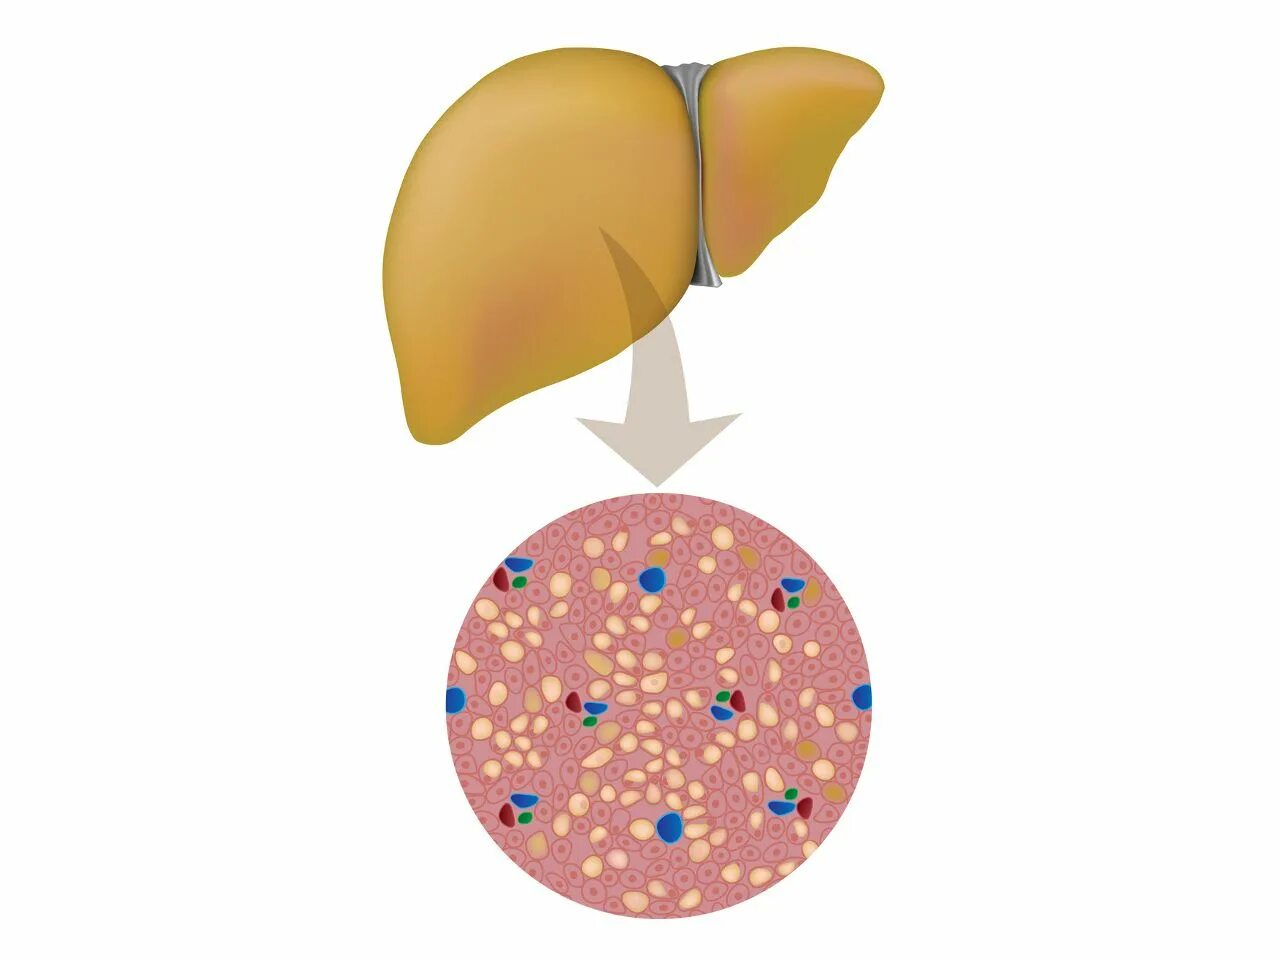

Диффузные изменения печени жировой гепатоз гепатомегалия